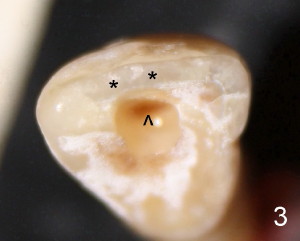

Initial access shows that the labial portion of the recessed pulpal horn (brown, < in Fig3 (occlusal view) is not fully exposed, while that the most lingual aspect of the incisal edge (between **) has been removed. Further access appears to be necessary to expose the obliterated pulpal chamber (Fig.7 <) and more of the incisal edge has been violated ( between **). With good exposure, the canal is easily found around the arrowhead (<) in Fig.7. Fig.11 shows the access after application of Gates-Glidden files. Before rotary files, the access is enlarged further both labially and lingually with diamond/carbide endo access burs (Fig.15). Traditional way to get access actually sacrifices more lingual structure (Fig.11,15 black <) than the labial one (white <). Return to main article